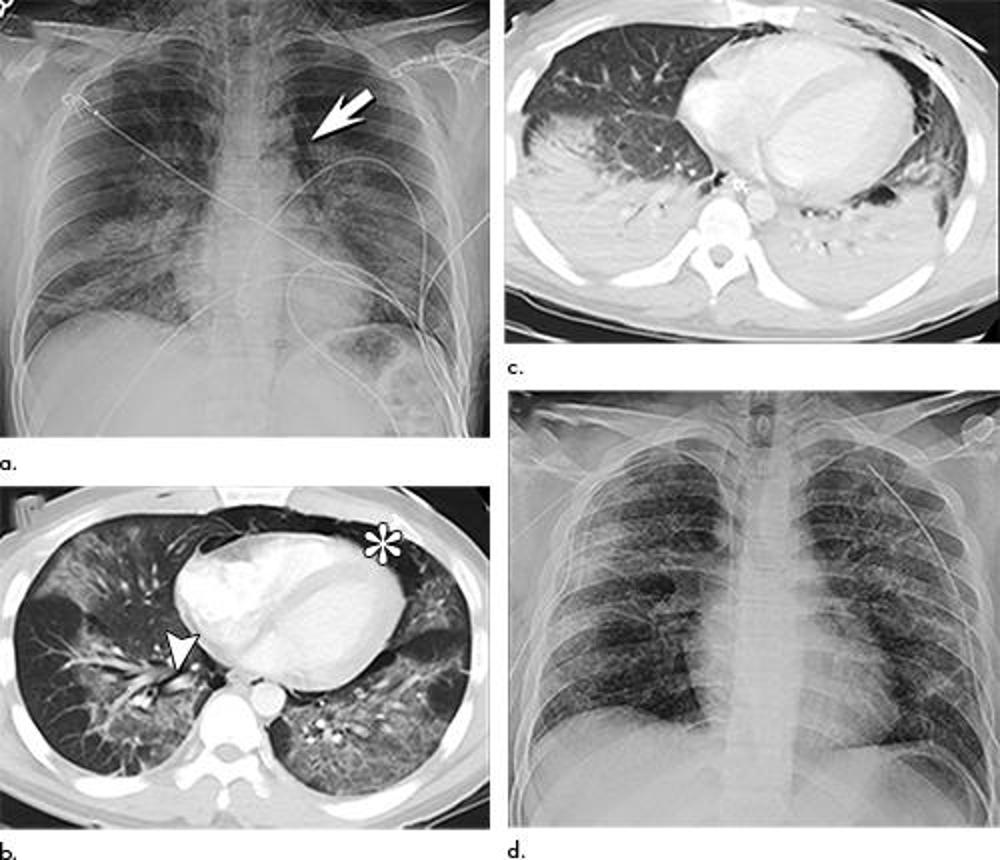

Figure 9. Electronic cigarette or vaping product use–associated lung injury in a 25-year-old man manifesting with spontaneous pneumomediastinum and acute lung injury. (a) Frontal chest radiograph at presentation shows bilateral perihilar opacities with pneumomediastinum (arrow) and subcutaneous emphysema. (b) Axial enhanced CT image through the lower lobes obtained at presentation shows multifocal bilateral ground-glass opacity and pneumomediastinum (*) with interstitial emphysema (arrowhead). (c) Axial enhanced CT image through the lower lobes obtained 5 days following presentation shows progression of lung abnormalities now with dense, symmetric, bilateral lower lobe consolidation with pneumomediastinum still present. (d) Frontal chest radiograph obtained 16 days after presentation shows improvement in the bilateral lung opacities, although residual abnormalities, which have migrated somewhat peripherally, remain. Pneumomediastinum has resolved.